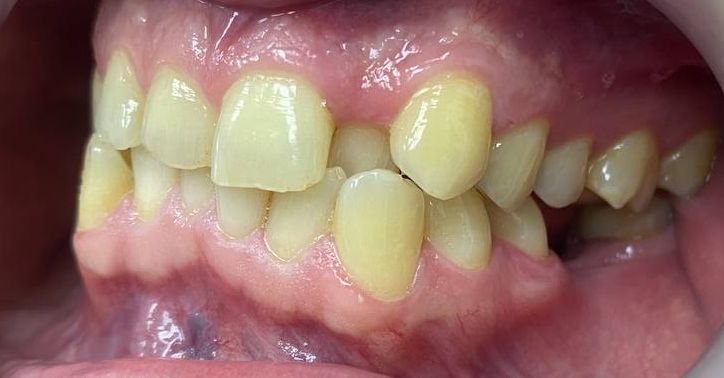

Palatal position of teeth is

characterized by the eruption of one tooth or a group of teeth outside the

dental arc on the palatal side. So, most often, incisors or second premolars

eruption.

(one or both) - 61.35%. In 57% of children, there are erased areas on the

incisal and vestibular surfaces of palatal-displaced teeth as a result of the

functional action of antagonist teeth. With a slight overlap, abrasion of the

cutting edge and shortening of the abnormally located tooth are observed. In the

palatal location of the upper jaw incisors, flattening of the frontal area of

the upper jaw and lengthening of the frontal area of the lower jaw are

determined. In this case, exposure of the necks of the lower frontal teeth,

violation of their stability and inflammation of the gums may be observed, and

the clinic of catarrhal or atrophic gingivitis develops as a result of

functional trauma.